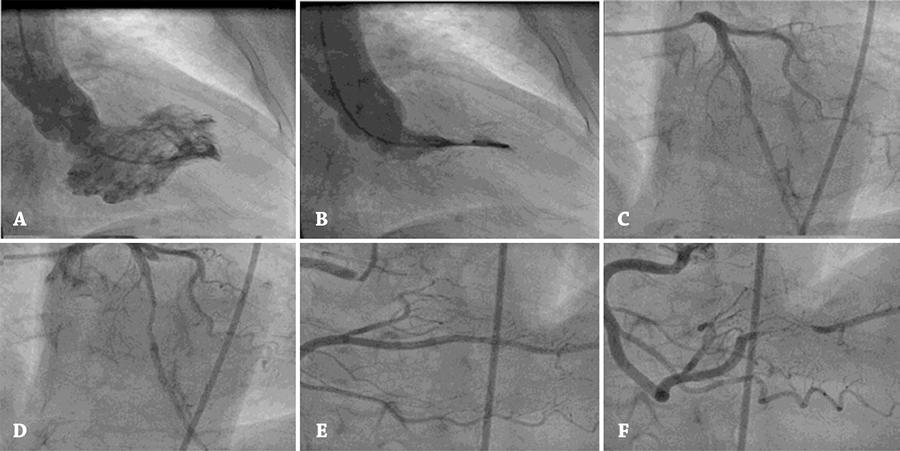

Paciente de 62 anos de idade, sexo feminino, portadora de hipertensão arterial e história de angina do peito, desencadeada por estresse emocional há 4 meses. O eletrocardiograma mostrava hipertrofia ventricular esquerda e alterações da repolarização ventricular. A cineangiocoronariografia mostrou importante hipertrofia ventricular esquerda sem gradiente intracavitário e a presença de ponte miocárdica comprometendo o terço médio da artéria descendente anterior e da coronária direita, em seu ramo descendente posterior. A ponte miocárdica tem como localização quase exclusiva a artéria descendente anterior. Relatos comprometendo a artéria circunflexa são raros e mais ainda a coronária direita.